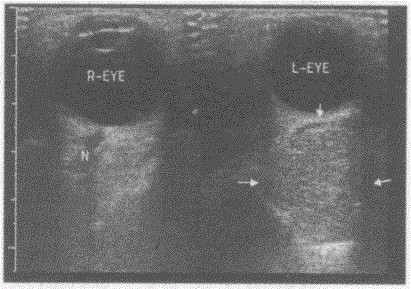

问题 临床资料:男,49岁,自述左眼胀不适6个月,进行性眼球向外突出,视力下降。超声综合描述:左眼球后可见5.1cm×4.6cm圆形中等回声区(箭头所示),边界清晰,内回声不均,探头轻压前后径稍小,视神经被挤向鼻侧,CDFI:内未见明显动静脉血流信号。 超声提示:

选项 A.左眼脉络膜黑色素瘤 B.左眼球后海绵状血管瘤 C.视神经母细胞瘤 D.球后正常声像图

答案 B